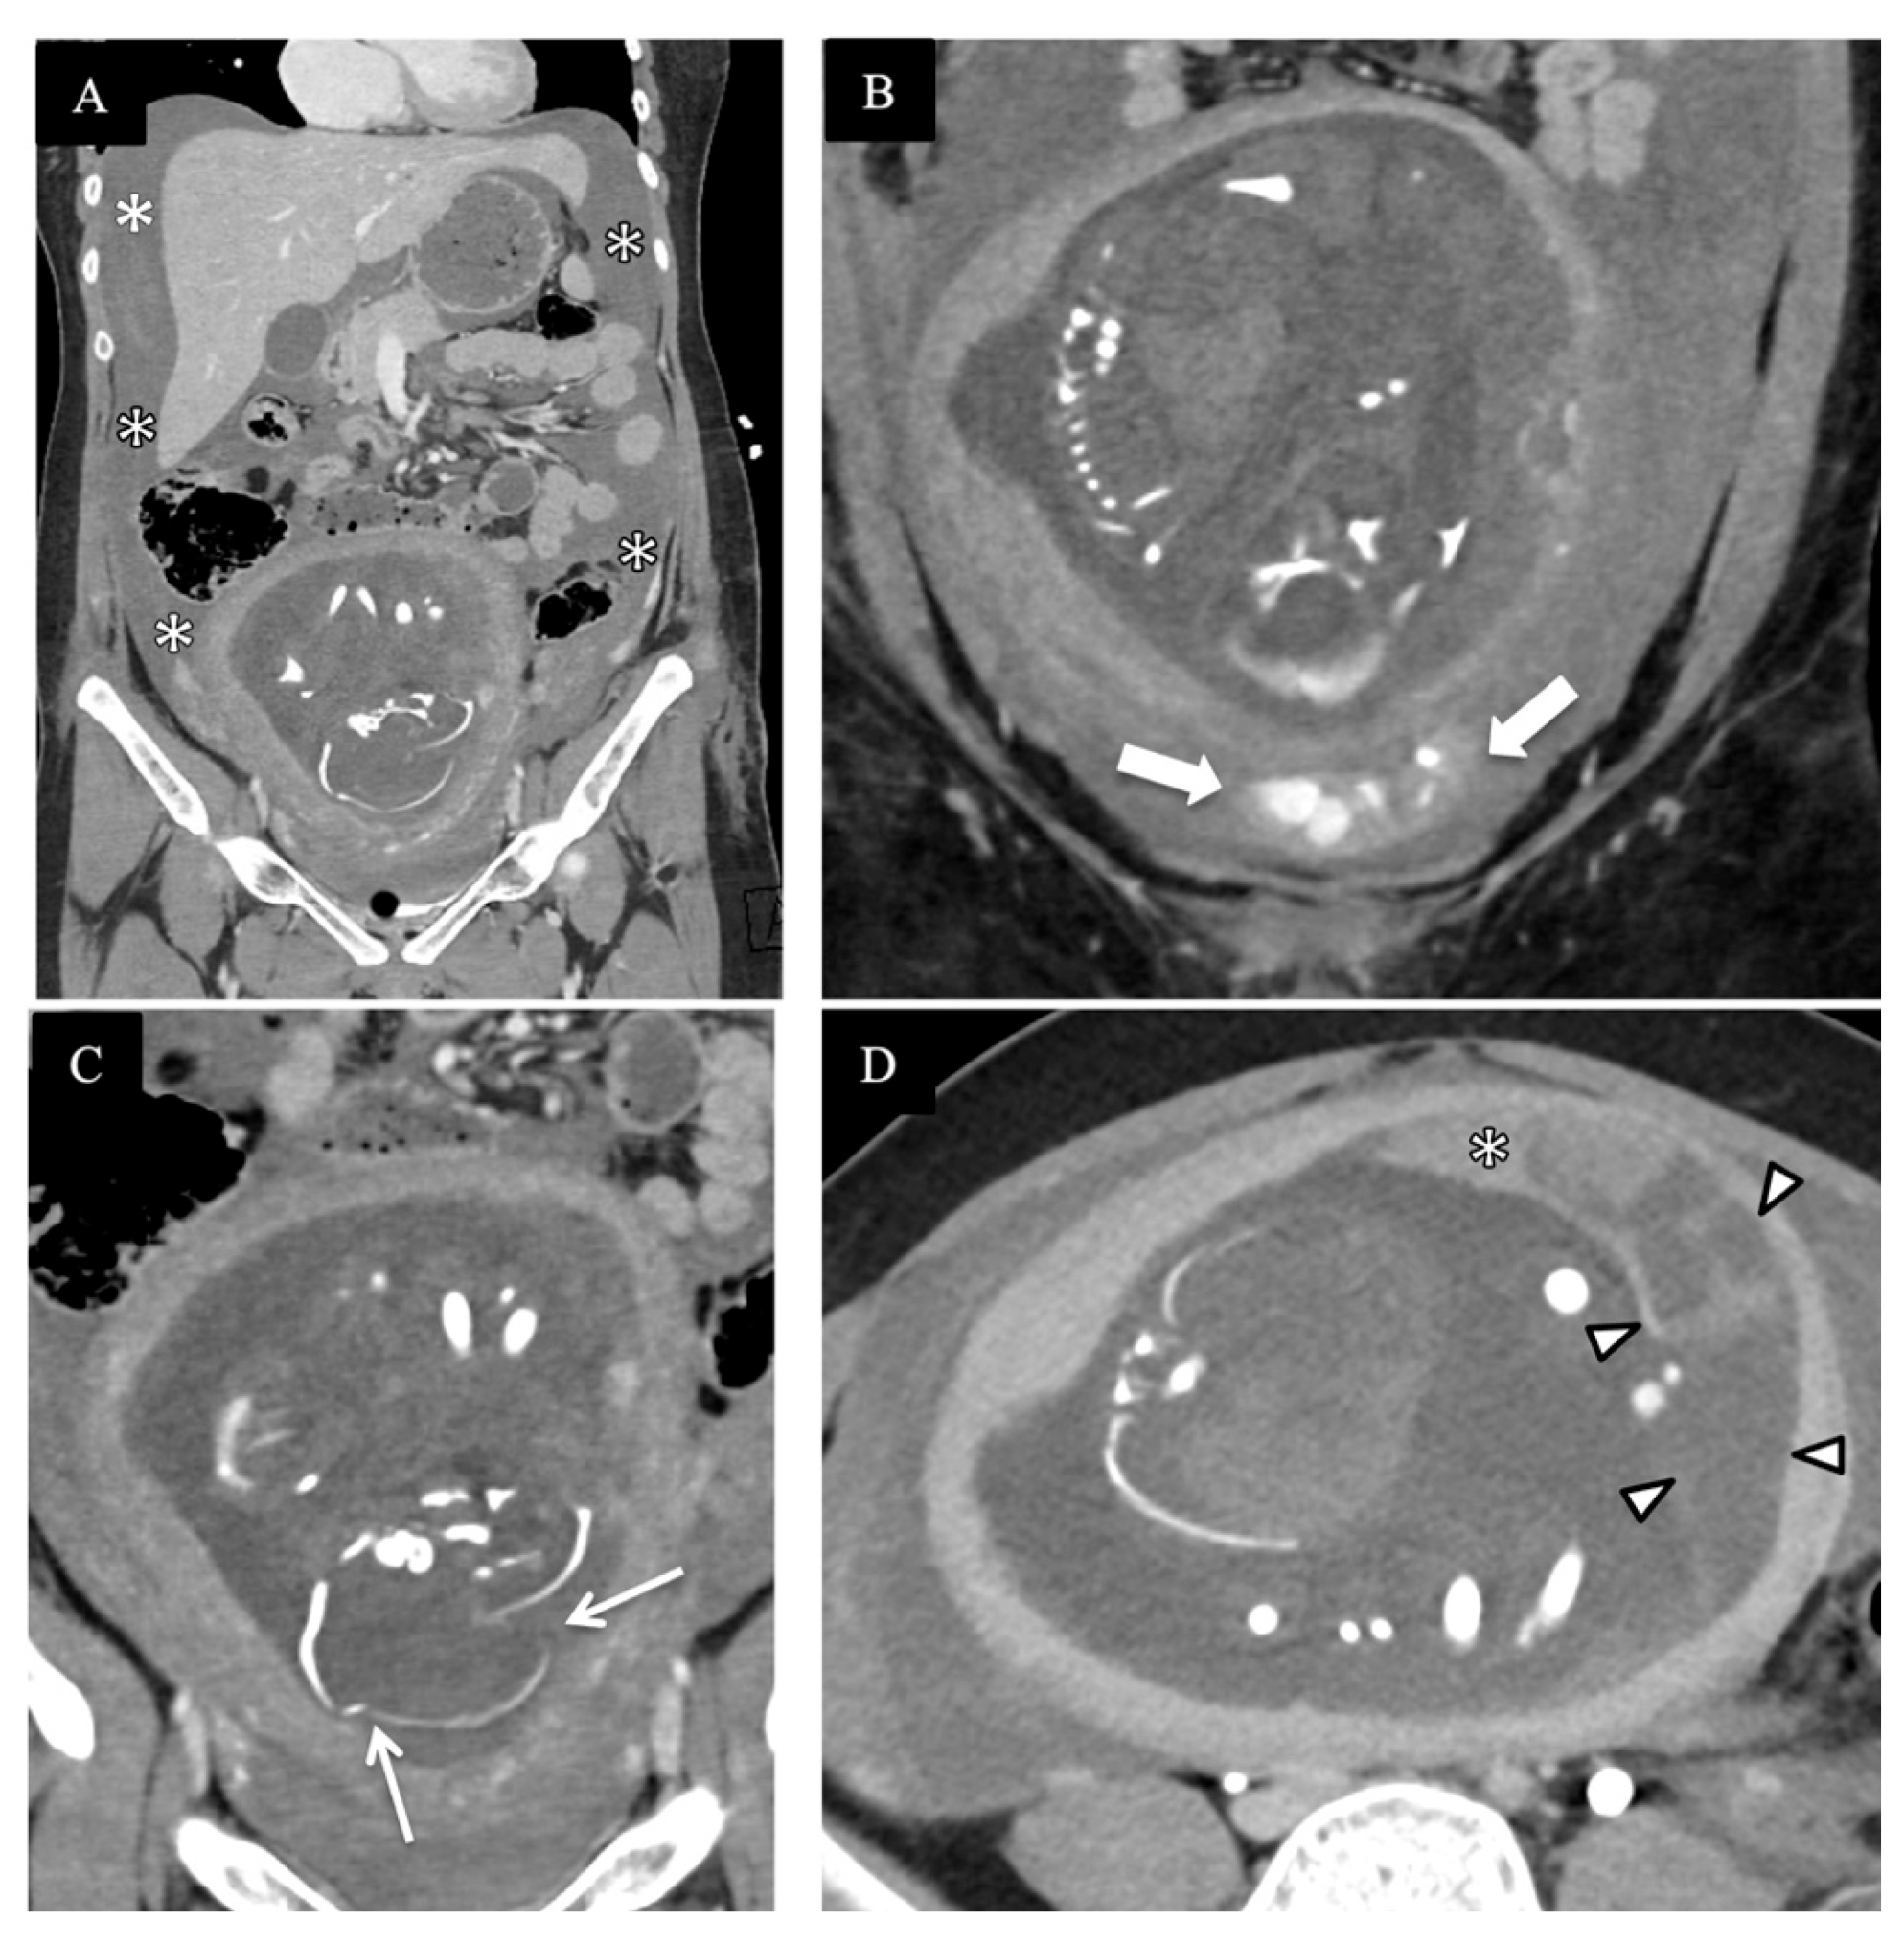

4. Review of Local Presentations